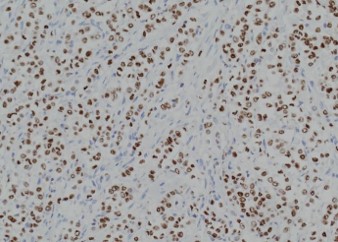

Pathology of the right hemicolectomy specimen was “involvement by metastatic carcinoma, immunoprofile compatible with breast primary”. The cytokeratin profile was CK7+, GATA3+ and MOC-31+, and negative for CK20 and CDX-2. There was very focal positivity for E-cadherin, while p120 catenin mostly showed cytoplasmic staining in the tumour cells. Microscopic examination suggested that the tumour invaded from mucosal side of the intestinal towards the serosa; the proximal and distal resection margins were clear. The morphology and immunoprofile point towards a metastatic carcinoma of breast.